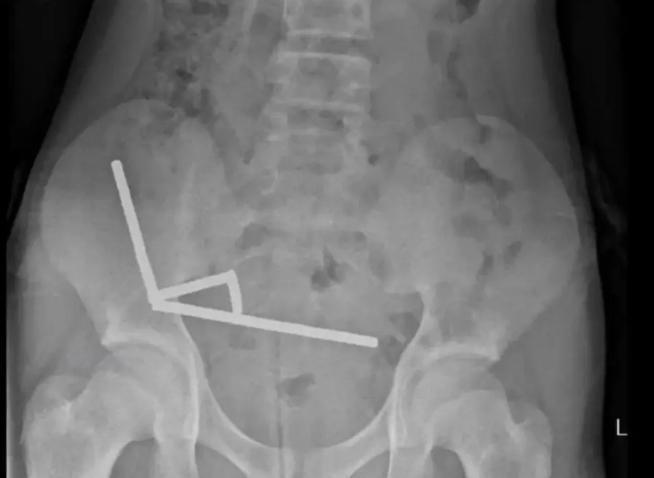

X光中顯示,這些小磁鐵在他腸子裡的不同部位中形成4條鏈子互相拉扯,並切斷了附近組織的血流,壓力更導致多處壞死。

醫生為他移除磁鐵和部分受損腸道,男童最終在醫院裡住了8天。